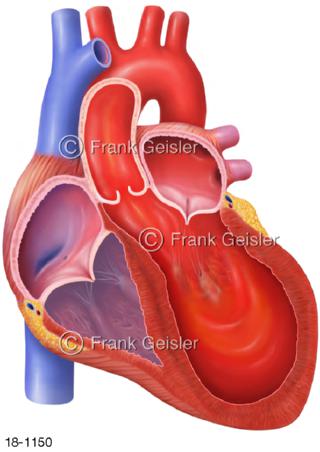

18-1150 Herz mit Takotsubo Stress-Kardiomyopathie